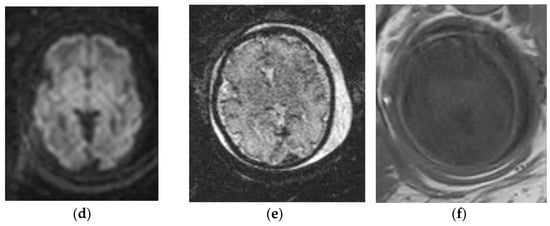

3.1.2. Chiari II Malformation

- Stevenson, K.L. Chiari Type II malformation: Past, present, and future. Neurosurg. Focus 2004, 16, 1–7. [Google Scholar] [CrossRef]

- Van den Hof, M.C.; Nicolaides, K.H.; Campbell, J.; Campbell, S. Evaluation of the lemon and banana signs in one hundred thirty fetuses with open spina bifida. Am. J. Obstet. Gynecol. 1990, 162, 322–327. [Google Scholar] [CrossRef]

- Sutton, L.N.; Adzick, N.S.; Bilaniuk, L.T.; Johnson, M.P.; Crombleholme, T.M.; Flake, A.W. Improvement in hindbrain herniation demonstrated by serial fetal magnetic resonance imaging following fetal surgery for myelomeningocele. J. Am. Med. Assoc. 1999, 282, 1826–1831. [Google Scholar] [CrossRef] [Green Version]

- Nagaraj, U.D.; Bierbrauer, K.S.; Zhang, B.; Peiro, J.L.; Kline-Fath, B.M. Hindbrain Herniation in Chiari II Malformation on Fetal and Postnatal MRI. AJNR Am. J. Neuroradiol. 2017, 38, 1031–1036. [Google Scholar] [CrossRef] [PubMed] [Green Version]